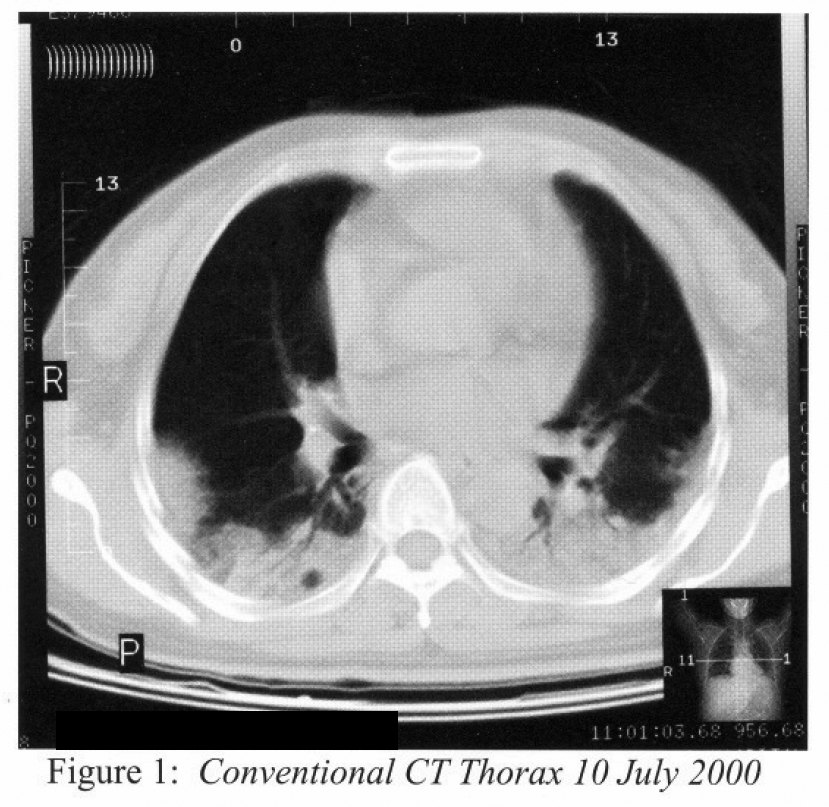

Blood gas repeat on 10/07/00 showed hypoxaemic failure with pH 7.5, PaCO2 4.32 kPa and PaO26.25kPa. CT pulmonary angiogram was done on 10th July 2000 that showed no major vessels embolus. A concomittent conventional CT of thorax (Figure 1) showed peripheral alveolar shadows over subpleural areas.